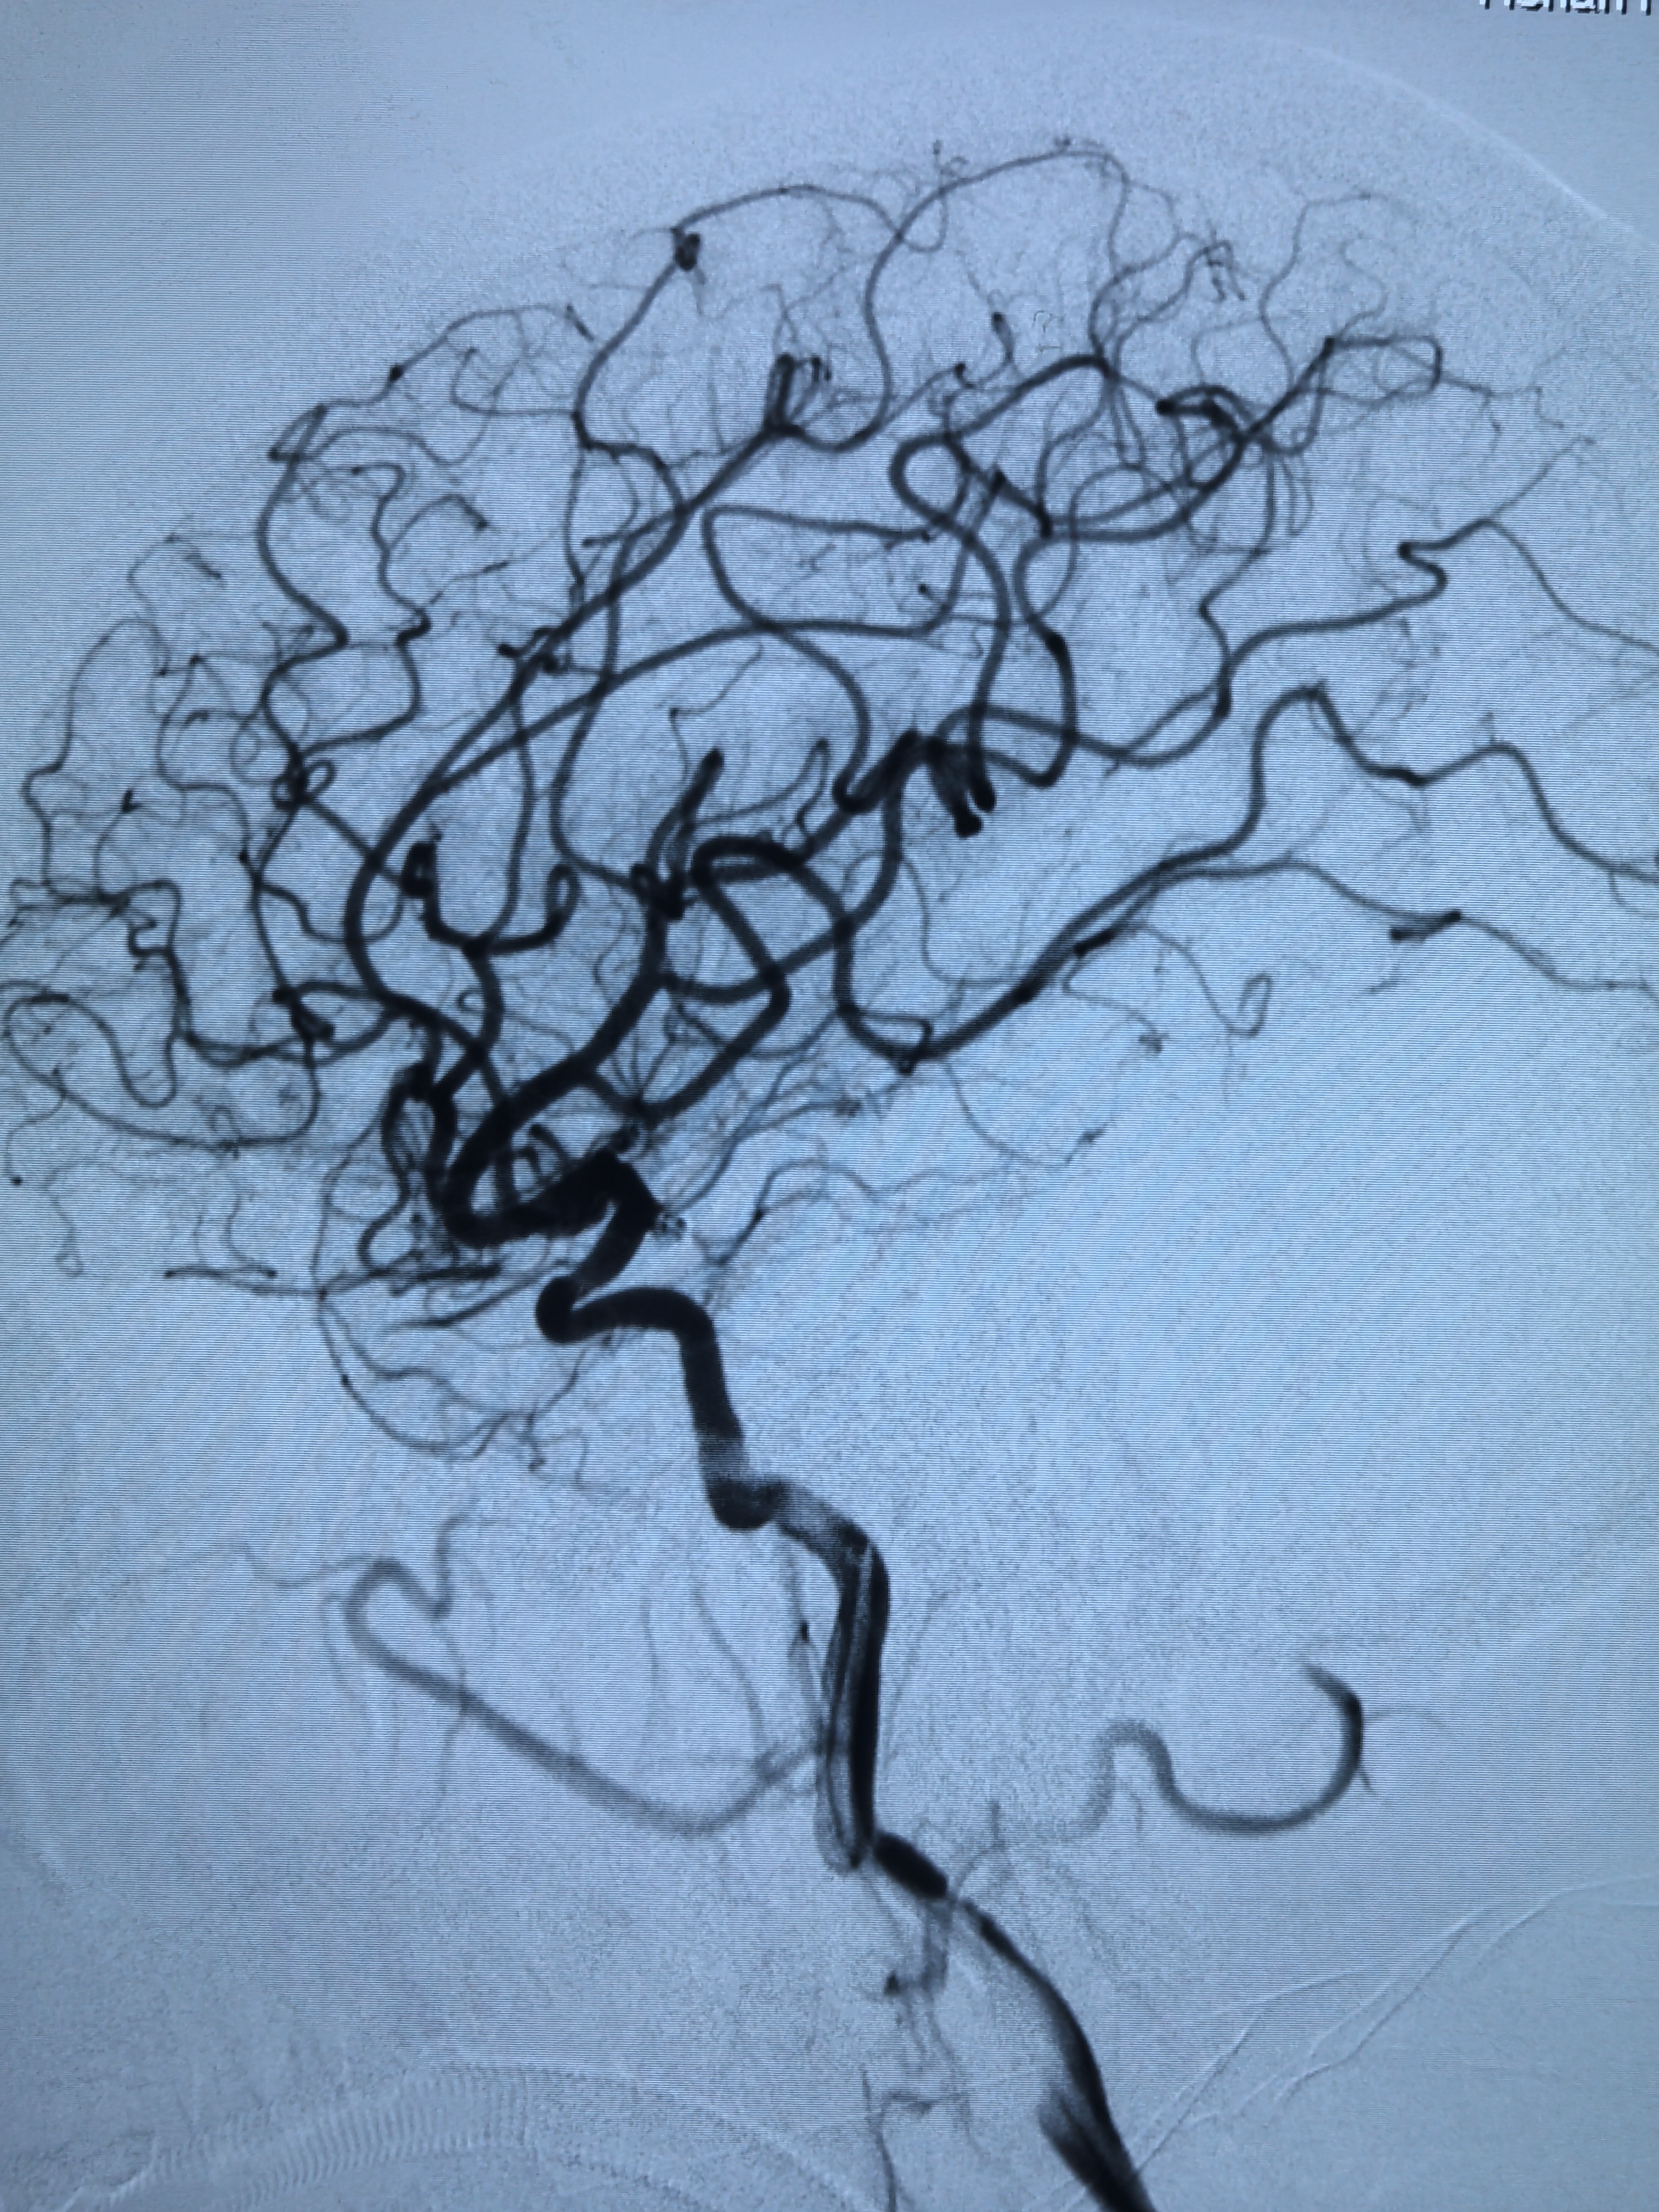

右侧颈内动脉脉前动脉瘤单栓!